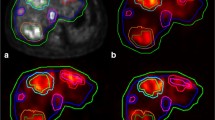

Six patients had an extrahepatic deposition of the 166Ho scout dose (Figs. 1, 2, 3, 4, 5 and 6): one HEPAR, three HEPAR 2, one HEPAR PLUS and one SIM candidate [4,5,6,7]. Baseline characteristics can be found in Table 4. Median LSF (of these patients) was 13.3% (range 9.4–17.6). Median follow-up was 4 months (range: 1–12 months).

A 56-year-old male with a primary rectal neuroendocrine tumour, liver and bone metastases. (a) Digital subtraction angiography of 166Ho scout dose procedure. (b) Corresponding 166Ho scout dose SPECT/CT. (c) Corresponding cone beam CT. All images show extrahepatic deposition and contrast blush in gastric fundus (arrows). After coiling of accessory left gastric artery, extrahepatic deposition on SPECT/CT and contrast blush on cone beam CT disappeared (images not shown). Accessory left gastric artery originated distally from left hepatic artery, running through the ligamentum venosum towards the gastric fundus [16]